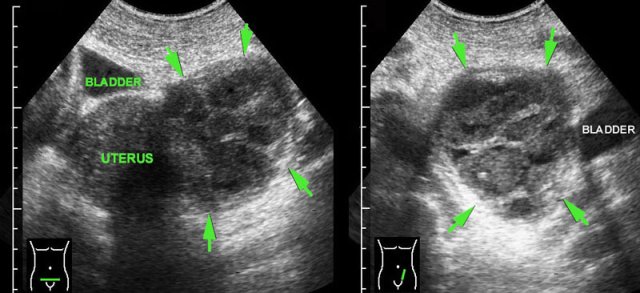

Ischemic myoma

case 1

This 25 year old pregnant woman presented with a palpable, painful mass in the RLQ, suspect for an “appendiceal mass”.

US revealed a hypoechoic, inhomogeneous, hypovascular round solid mass arising from the myometrium, and “bulging” into the abdominal wall during compression.

The

diagnosis was an ischemic myoma.

She was successfully treated

with analgesics.

case 2

Here another case of an ischemic myoma.

The extrinsic location in this case suggests that this is a

pedunculated myoma (arrowheads).

This patient was successfully treated with analgesics and labor inhibitors.